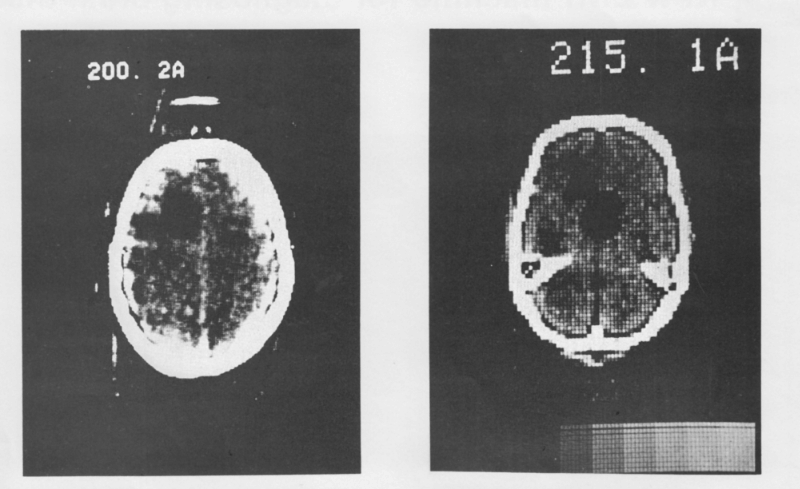

На снимке 200.2A была изображена женщина средних лет, пациентка из больницы Аткинсона Морли с подозрением на опухоль в левой лобной доле. Опухоль была успешно иссечена и подтверждена как кистозная астроцитома.

Исследователи установили полноразмерный сканер в лондонской больнице Аткинсона Морли и 1 октября 1971 г. под контролем Амброуза было проведено первое сканирование

Поэтому весь процесс оказался долгим. Полчаса заняло самое сканирование, затем Хаунсфилд с магнитными лентами, куда записались данные, поехал через весь город, чтобы обработать их на компьютере EMI. Это заняло еще 2,5 часа. И наконец, получение изображений с помощью фотоаппарата Polaroid и возвращение в больницу.

Амброуз вспоминал, что сканирование дало четкое представление о нахождении кисты. Когда снимки были готовы, они с Хаунсфилдом чувствовали себя как футболисты, только что забившие победный гол.